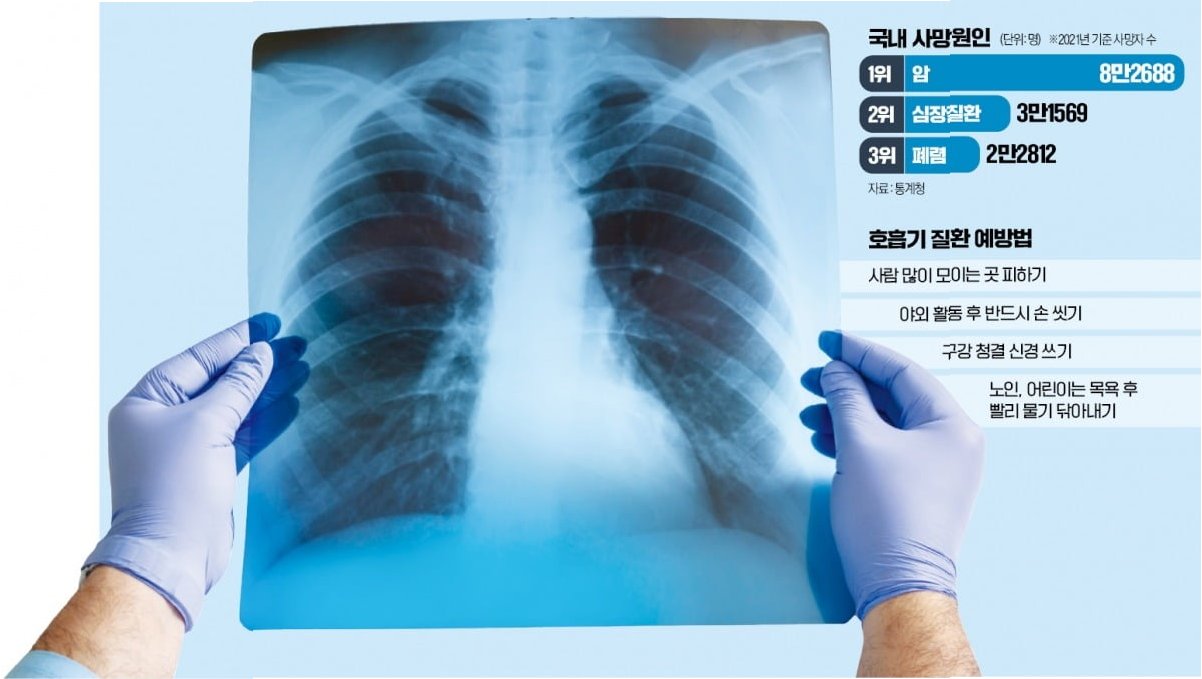

폐렴은 예방이 매우 중요합니다. 고령층은 폐렴구균 백신, 인플루엔자 백신 접종을 통해 폐렴 발생 위험을 줄일 수 있습니다. 또한, 구강 위생 관리를 철저히 하고, 규칙적인 식사와 운동을 통해 면역력을 강화해야 합니다. 흡인성 폐렴 예방을 위해, 식사 시에는 앉아서 천천히 먹고, 음식물을 삼키기 어려울 경우 전문가와 상담하여 적절한 조치를 취해야 합니다. 젊은층은 개인 위생 관리를 철저히 하고, 감염 위험을 줄이기 위해 마스크 착용, 손 씻기 등을 생활화해야 합니다. 충분한 휴식과 수면을 취하고, 스트레스를 관리하며, 금연하는 것이 중요합니다. 건강한 식습관과 규칙적인 운동을 통해 면역력을 강화하는 것도 폐렴 예방에 도움이 됩니다.